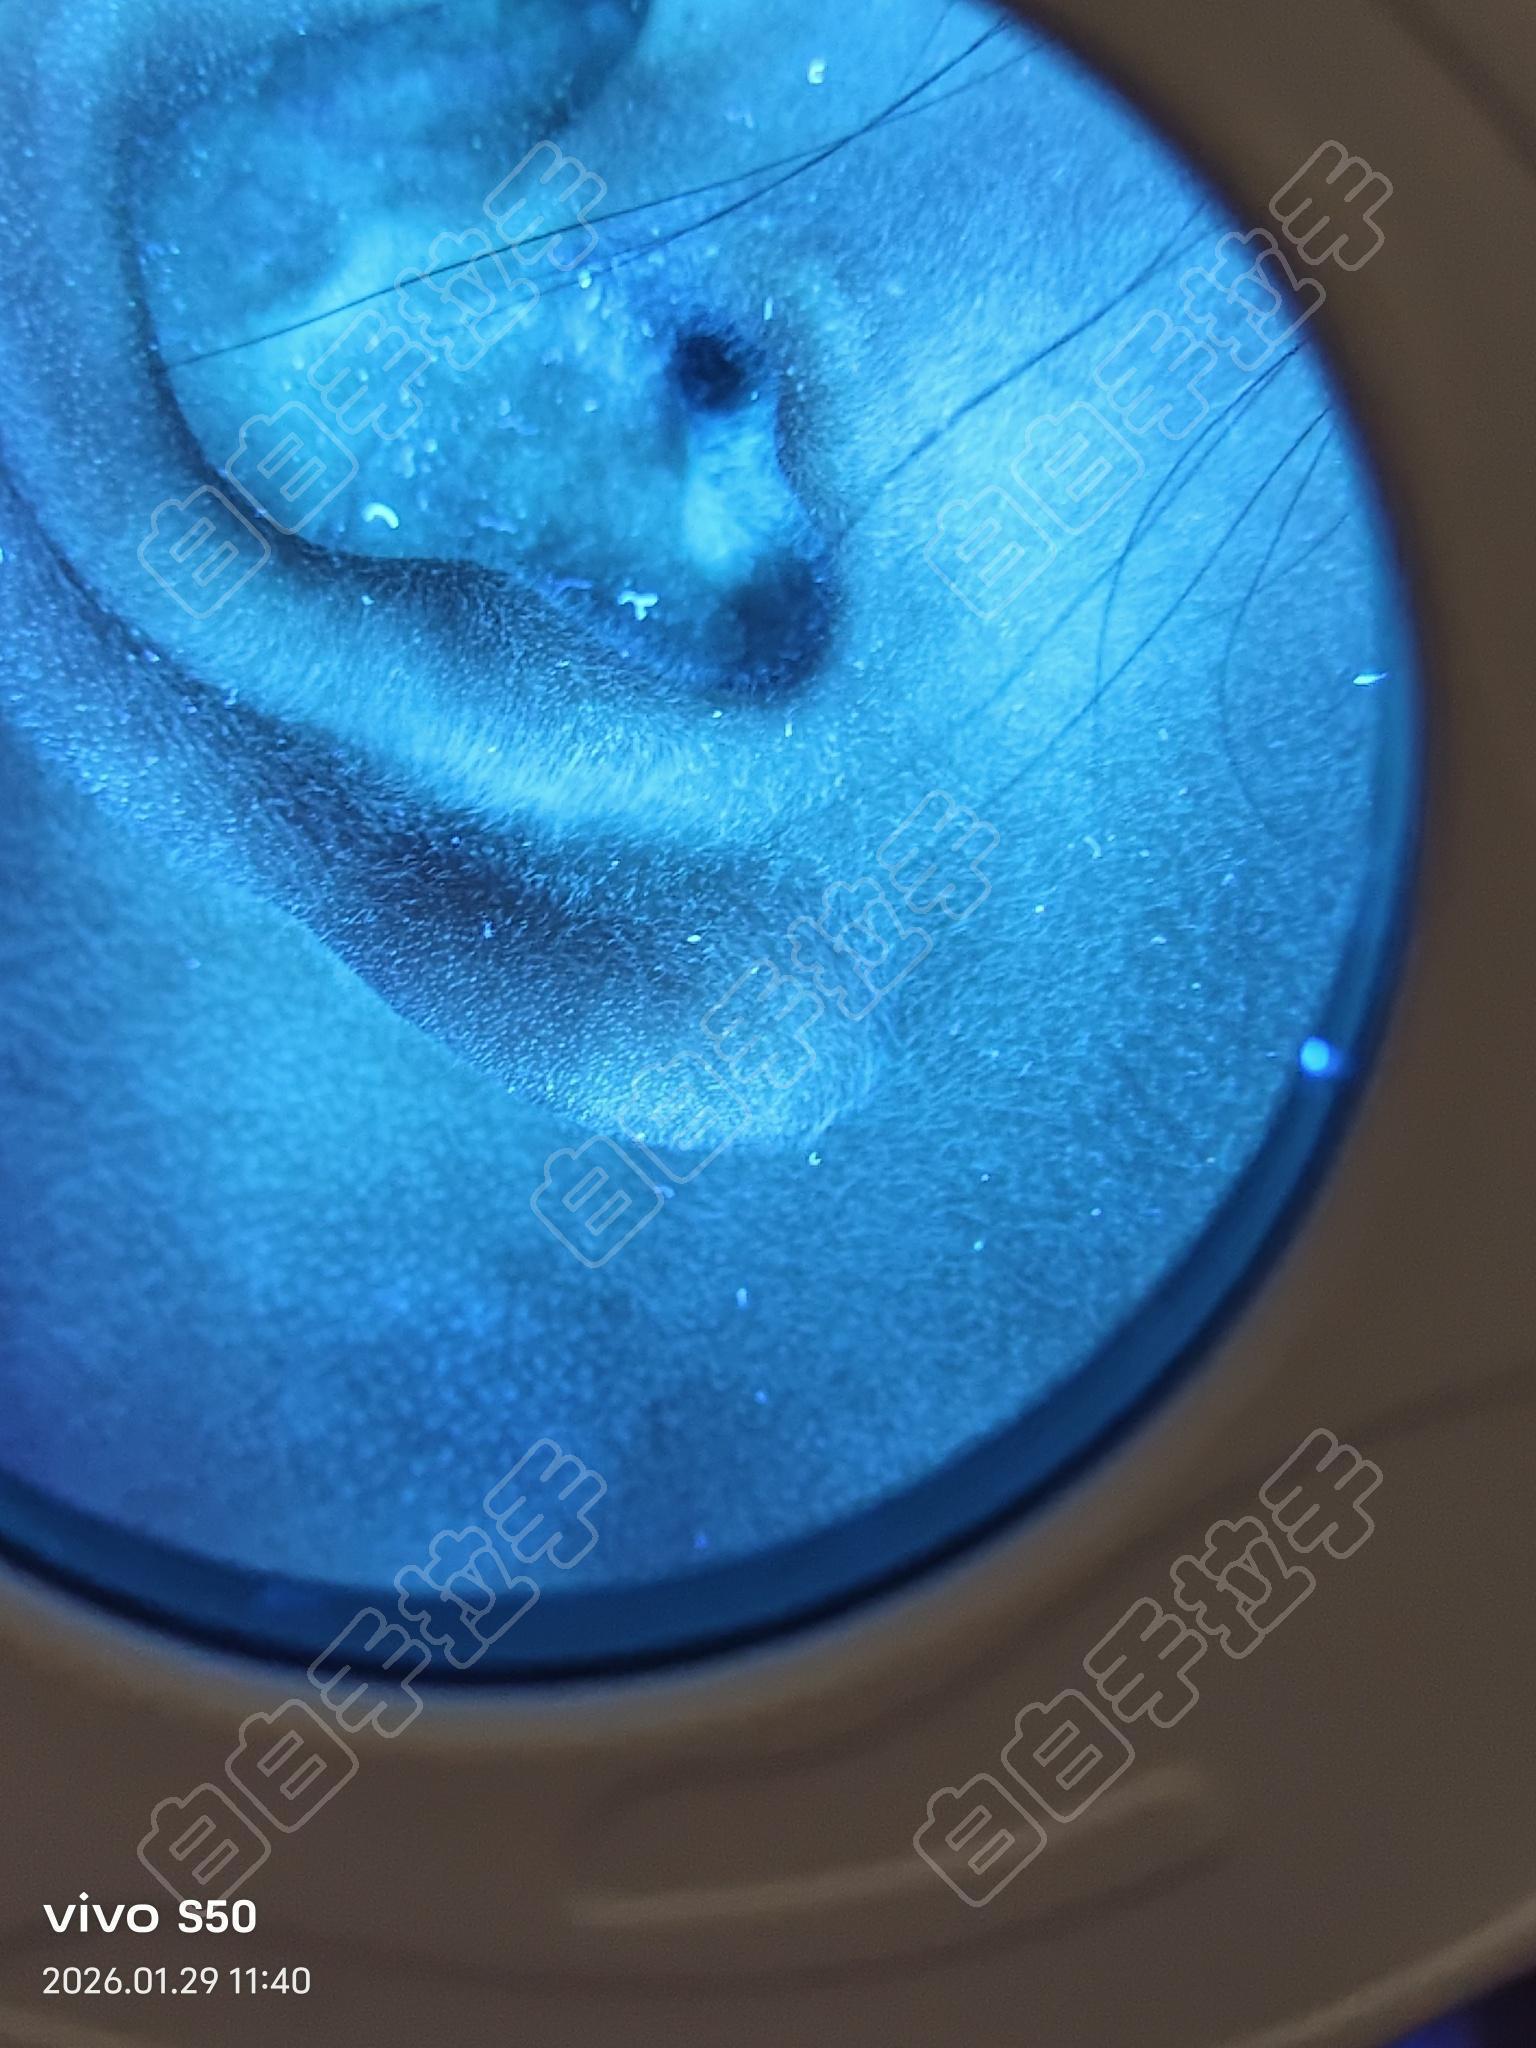

[已解答] 求助,耳蜗里面怎么照光?

耳朵里面偶然间发现的 ,汗毛变白了,这种怎么居家照光,有没有白友在耳蜗里面的,感谢

耳道里面有荧光的地方

这个不算荧光,不够亮!除非你照片像素的问题,而且肉眼可见的没什么异常!

你自己白天拍一个清晰一点儿的发来看下,目前看着真没觉着有什么异常的!一方面是没看到明显色差,另外一个就是耳蜗里边肤色偏淡很正常!如果是专科医院检查的不排除医生医德或者医术问题。